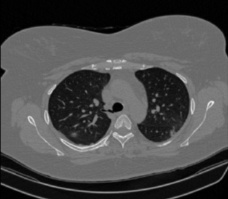

It should be mentioned that for explainability purposes [7, 8, 9], an anchor set was generated for the COV19-CT-DB database [5]. This included 11 anchors, each representing a respective 3-D CT scan obtained through an appropriate clustering procedure. Figure 2 shows a series of slices from a COVID-19 case, whereas Figure 3 shows a series of slices from a non COVID-19 case.